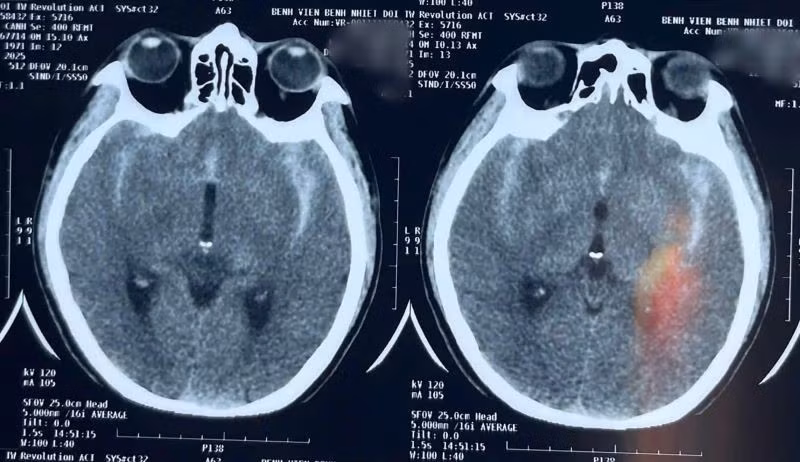

Chụp CT não khẩn cấp cho thấy bệnh nhân có xuất huyết dưới nhện lan tỏa hai bên - dấu hiệu điển hình của vỡ phình động mạch não. Kết quả chụp phim dựng hình mạch máu não xác định người bệnh có hai túi phình, trong đó túi phình động mạch thông trước đã vỡ, túi phình còn lại ở não trước kích thước nhỏ.

Chụp CT não khẩn cấp cho thấy bệnh nhân có xuất huyết dưới nhện lan tỏa hai bên - Ảnh BVCC